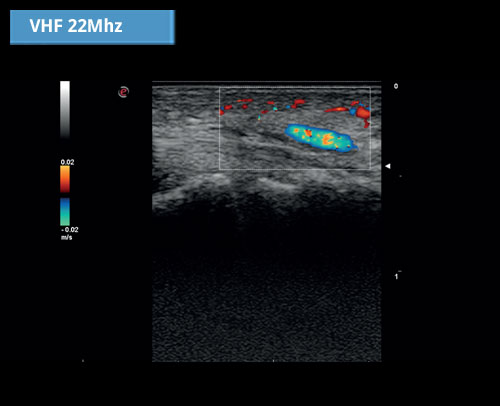

Velmi vysoká frekvence 22 MHz: Extrémně kvalitní zobrazování a barevný doppler při velmi povrchových aplikacích